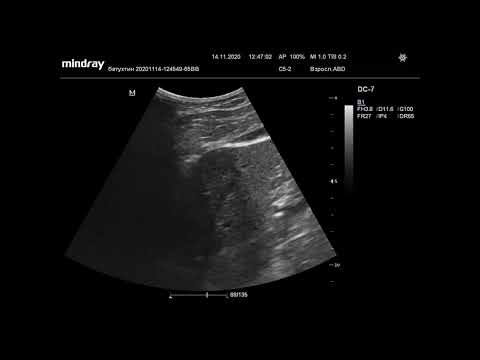

Ультразвуковая диагностика. Доктор Иогансен. Видеопримеры. Выпуск 5. Киста поджелудочной железы.

Представлены видеопримеры кисты головки поджелудочной железы, выявленной при ультразвуковом исследовании. Ссылка на Дзен: Ссылка на RuTube: Ссылка на VK видео: Ссылка на YouTube: / @dr.johansen